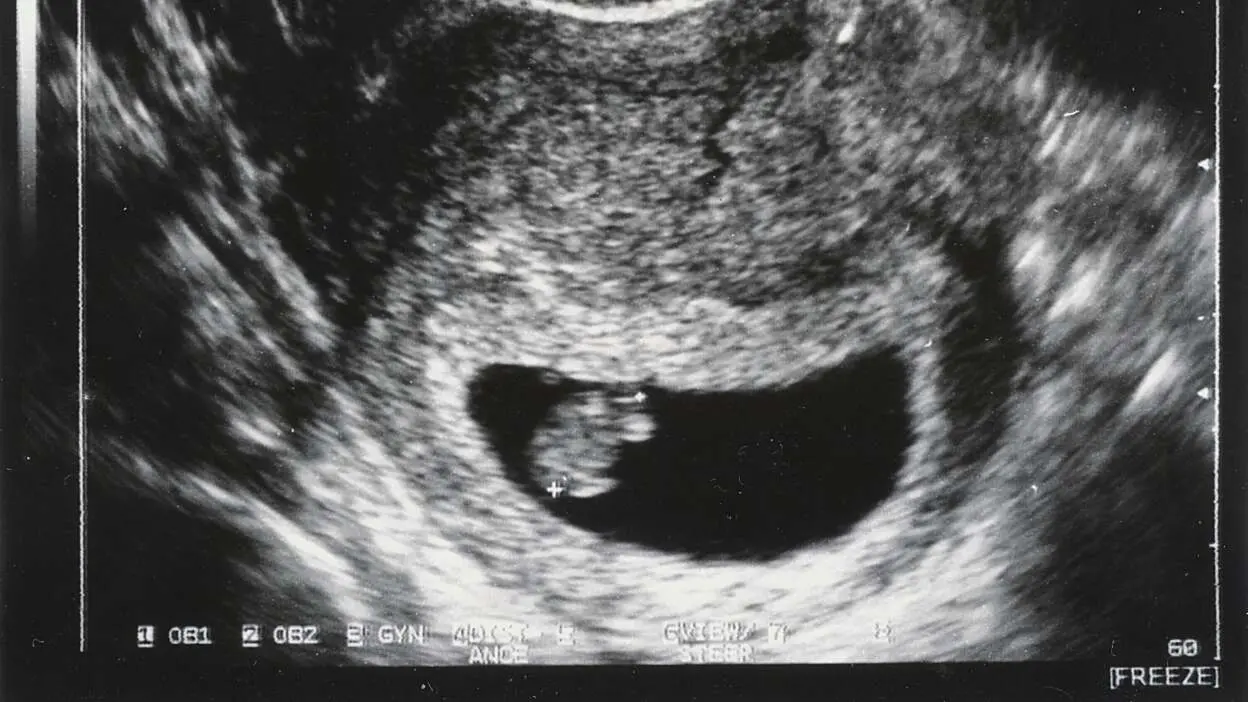

Isso porque a idade gestacional (semanas de gravidez) não é quanto tempo você teve um embrião ou feto em seu corpo, mas quanto tempo se passou desde o primeiro dia da sua última menstruação . Vamos analisar isso, usando um exemplo clássico de uma mulher (vamos chamá-la de Jane) com um ciclo perfeito. Ela começa a menstruar em 1º de janeiro e faz sexo apenas uma vez na vida, resultando em uma gravidez. Essas datas variam de pessoa para pessoa, então este é apenas um exemplo:

- 21 de janeiro: O embrião em desenvolvimento se implanta em seu útero. Ela agora está grávida—especificamente, grávida de três semanas .

Então, o mais cedo que você pode saber que está grávida é na idade gestacional de “quatro semanas” — o que significa que o embrião foi implantado no seu útero por apenas uma semana real, e só existiu por duas semanas. Mas as datas são contadas como se a gravidez tivesse começado em 1º de janeiro.Este é um exemplo otimista, por muitas razões. Por exemplo, a menstruação da maioria das pessoas não vem em um ciclo de 28 dias. Se sua menstruação tende a vir em qualquer lugar entre, digamos, 29 a 34 dias, então você não vai começar a se perguntar até um pouco mais tarde. E isso pressupõe que você esteja olhando o calendário; se você não está esperando engravidar, você pode não perceber que está atrasada até uma ou duas semanas se passarem. A American Pregnancy Association observa que a maioria das mulheres descobre que está grávida com quatro a sete semanas de idade gestacional (que é de duas a cinco semanas após ter relações sexuais que resultam em concepção).